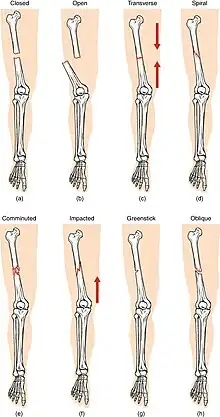

(a) closed fracture

(b) open fracture

(c) transverse fracture

(d) spiral fracture

(e) comminuted fracture

(f) impacted fracture

(g) greenstick fracture

(h) oblique fracture

In orthopedic medicine, fractures are classified in various ways. Historically they are named after the physician who first described the fracture conditions, however, there are more systematic classifications as well.